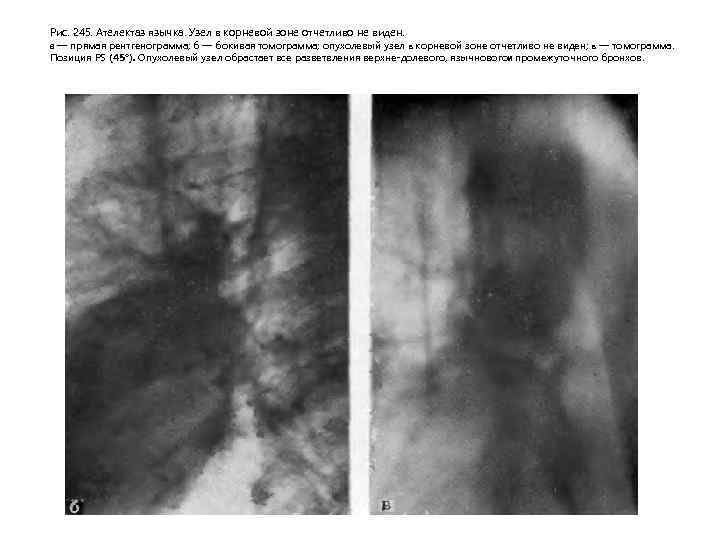

Четвертая фаза соответствует выраженной клинической и достаточно демонстративной рентгенологической картине заболевания. В этот период отчетливо виден опухолевый узел, иногда достигающий нескольких санти метров в диаметре. Связь узла с бронхом и прогрессирующий рост в сто рону последнего приводит к сужению просвета II степени и развитию обтурационной эмфиземы. Нередко при сравнительно быстром метастазировании опухоли в лимфа тические узлы видимая тень в легком представляет собой отображение первичного опухолевого узла, слившегося с метастатически измененными увеличенными лимфатическим узлами (рис. 244). При этом опухолевый узел в корневой зоне часто приобретает полициклические контуры. Обна ружение увеличенных трахеобронхиальных и паратрахеальных лимфати ческих узлов иногда приводит к неправильной расшифровке видимой кар тины, когда все изменения связываются с системным поражением лимфа тических узлов легкого и средостения. По мере развития болезни растет первичный опухолевый узел и стадия гиповентиляции, а затем клапанного вздутия, сменяющаяся ателектазом. Развитие ателектаза может привести к потере изображения опухолевого узла на фоне спавшегося сегмента или зоны. Возникновение ателектаза, так же как и при эпдобронхиальной опухоли, способствует развитию ряда осложнении, о которых уже говорилось. Наступает пятая фаза течения опухолевого процесса. При переходе от экспансивной к инфильтративной фазе роста опухоль начинает распространяться по ходу бронхов и сосудов, что находит своеотражение на рентгенограммах. При этом узел теряет свои четкие очерта ния, появляются грубые тяжистые тени, расходящиеся от опухолевого узла в легочную ткань (рис. 245).

Рис. 245. Ателектаз язычка. Узел в корневой зоне отчетливо не виден. а — прямая рентгенограмма; б — бокивая томограмма; опухолевый узел в корневой зоне отчетливо не виден; в — томограмма. Позиция PS (45°). Опухолевый узел обрастает все разветвления верхне долевого, язычновогои промежуточного бронхов.